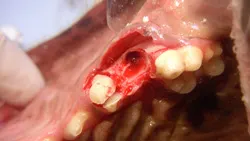

Step 12

Once all roots are removed (clinically and radiographically), each root alveolus is curetted and flushed with sterile saline and any bony protuberances are smoothed with a round, football-shaped, or tapered bur.

Step 13

The mucoperiosteal flap is now ready for closure over the extraction site (A). Note the triangular flap and triangular defect (B). If additional laxity in the gingival flap is needed for a tension-free closure, the underlayer of the flap (periosteum) can be incised with a scalpel blade or scissors.

A

Step 14

The site is radiographed postoperatively (A) and the mucoperiosteal flap is closed using absorbable suture in a simple interrupted pattern (B).